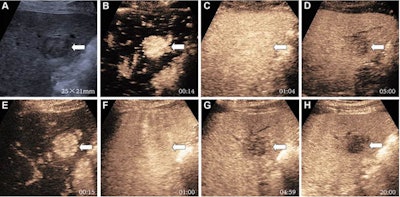

Pure blood pool agents such as sulfur hexafluoride microbubbles and Kupffer-cell agents like perfluorobutane microbubbles are the two main types of contrast agents used in ultrasound. Each agent has its own distinct advantages. On one hand, sulfur hexafluoride can't cross the vascular endothelium, which means that it generates pure vascular images. On the other hand, perfluorobutane can be specifically ingested by Kupffer cells in the liver, making way for additional lesion characterization in the Kupffer phase, more than 10 minutes after contrast injection. (Lesions that don't have functioning Kupffer cells show a defect in images.)

Li and colleagues previously demonstrated that a modified CEUS method using perfluorobutane had high accuracy in diagnosing liver cancer. This method classifies certain liver observations as LI-RADS-5 rather than LI-RADS-4 or LI-RADS-M (probable or definite malignancy) based on Kupffer-phase findings.